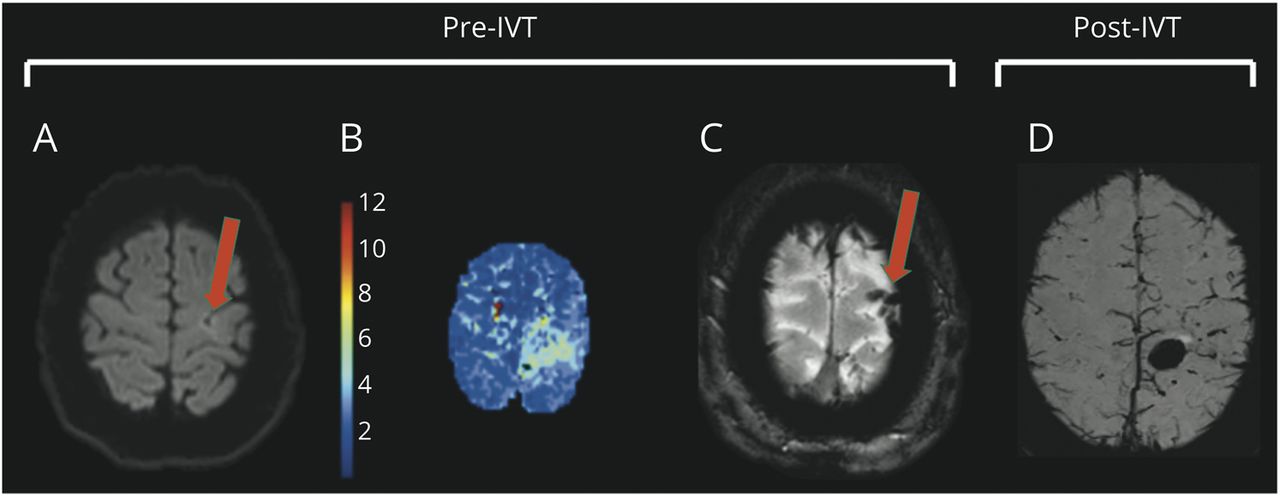

体格检查,症状出现180分钟后,患者有轻度右臂和右腿轻瘫。生命体征正常,没有任何血压升高的迹象。眼底检查结果正常。脑MRI显示左中央前回中度扩散受限和灌注不足,解释为急性动脉缺血性脑卒中(图1,A和B)。磁共振血管造影(MRA)显示颅内动脉多段不规则,无明显狭窄或闭塞(图2一个)。我们在症状出现225分钟后开始用rtPA静脉溶栓,没有临床改善。

(A) DWI序列显示中央沟边缘周围有高信号(箭头)。(B) TMax灌注图,显示相应区域达到最大灌注所需时间。(C) SWI序列显示皮质静脉血栓形成(箭头)。(D) SWI序列显示出血性转化。DWI =扩散加权成像;IVT =静脉溶栓;SWI =磁化率加权成像。

第二天,对照MRI在原发性缺血区域内发现左侧中央前回实质出血,未见肿块效应或临床恶化。MRI还显示左额叶皮质静脉血栓形成(实际上在基线成像上出现)(图1 c左横窦血栓形成。MRA证实颅内动脉(双侧大脑中动脉和左侧大脑前动脉)持续不规则,经颅多普勒(TCD)检查证实,发现血流速度增加表明右侧大脑前动脉狭窄超过50% (图2 b)。

在急诊科的初步评估中,由于MRI显示皮质扩散受限小,我们认为患者为缺血性中风(图1)并给予相应的静脉溶栓治疗。然而,在我们的患者中所见的比例偏瘫可能来自深部脑卒中,如内囊或脑干的卒中,以及脑皮层区域的缺血性病变图1反而会引起局灶性运动缺陷,局限于受影响皮质区域对应的皮质表征。